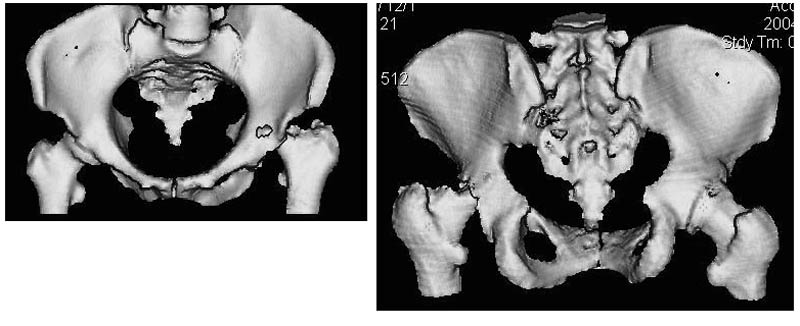

Женщина, 45 лет. В марте перенесла левосторонний коксит неизвестной этиологии. Специфику и онкологию исключили.

Интраартикулярных инъекций не было. Сейчас процесс клинически и рентгенологически - стабилизировался. Состояние вполне удовлетворительное.Предполагается тотальное эндопротезирование с пластикой полости аутокостью. Возможна ли бесцементная <чашка>? Заранее благодарю! С уважением,А.В.Владзимирский

Пртезирование через пол года после коксита закончившегося лизисом сустава, который на снимках выглядит как гнойный? Что значит неизвестной этиологии?

Уважаемый коллега! Последняя версия - мы пролистали ренгенологическую книженцию-так картинка вполне подходит под сустав Шарко (neuropatic joint ). В тазобедренном суставе патология редкая (но меткая). Ищите причину - варианты - нейросифилис, сирингомиелия, опухи спинного мозга (и выше тоже) компрессия спинного

мозга извне, рассеяный склероз, алкоголизм. А так-же : склеродерма ,Рейно,ревматоидный артрит, амилоидная инфильтрация нервов,и это не считая всяких менингеомиелоцеле,asymbolia,Riley-Day syndrom,и все возможные другие нейропатии. На данном этапе не спешите оперировать(протезирование протиопоказано при нейропатических суставах),проконсультируйтесь с классным невропатологом,сделайте МЯР головного озга и

весь позвоночник. И держите нас в курсе - случай крайне интересный :)